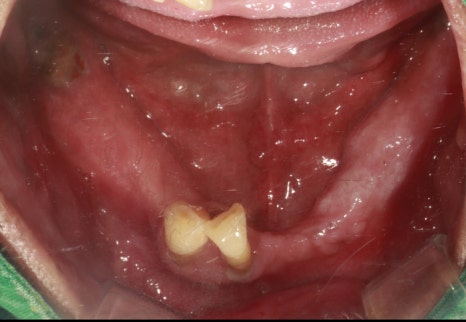

초진사진

촬영:2023년 9월 25일

한 번도 치과 방문을 하지 않았고

치아가 자연스레 부러지고 빠졌던 만큼

환자분의 치아 상태는 생각보다 심각했습니다.

살짝만 건드려도

충치로 인해 치아가 삭아 으스러질 것 같이 치아 조각이 떨어져 나오고 (치아우식)

어떤 치아는 흔들림이 매우 심했습니다(치주염)

건강한 치아들과 비교해 보면

잇몸과 잇몸뼈가 단단하게 잡아주는 치아가 하나도 없는 상태입니다.

그리고 어금니가 없다 보니

수직 고경(위턱과 아래턱 사이의 거리)이 완전히 무너진 상태이고

앞니가 너무 흔들거리고 솟아올라와서 걸리지 않게 씹기 위해서

씹는 동작도 비틀어서 하는 상태였습니다.

앞니만 조금 남아있고

어금니가 없음에도 불구하고

틀니조차 사용하지 않으셨던 환자분이라

식사하는데 많이 불편하셨을 것 같네요.